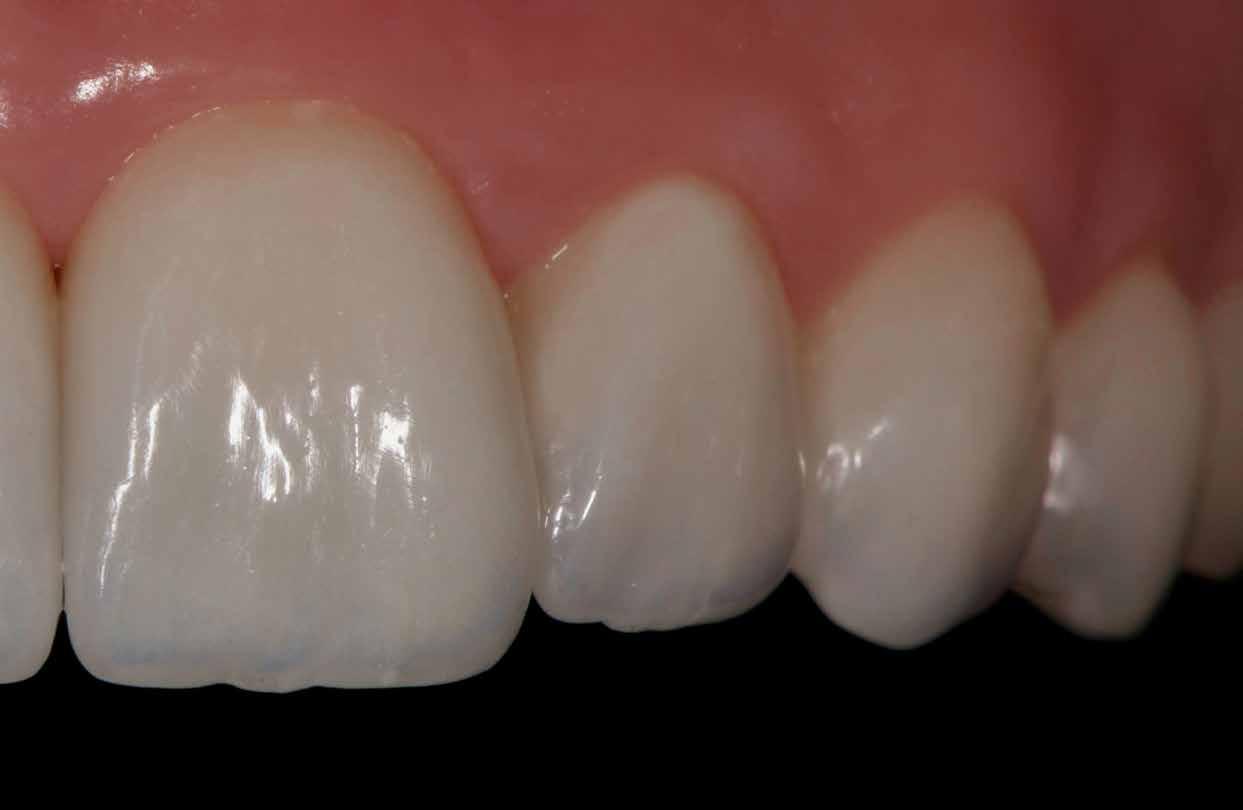

Végezetül részletfelvételek egy másik ragasztott hídról, amely hasonló módon készült, hat hónappal a behelyezés után (42–43. képek)

A hídtag enyhe mozgathatósága miatt az íny stimulálva volt. Ezzel a vérellátás további segítséget kapott, ami a lágyszövet kiváló adaptálódását hozta magával.